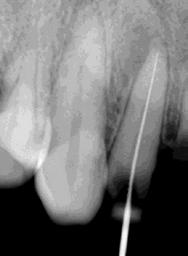

Las Figuras 4-13 son imágenes radiográficas de los dientes de la paciente que presen tan múltiples lesiones periapicales como consecuencia de las necrosis pulpares originadas por la radioterapia. Se realizaron los

tratamientos y retratamientos endodónticos necesarios para preservar los dientes en boca, evitando las exodoncias y por lo tanto minimizando el riesgo de generar osteorradionecrosis.

La Figura 14 muestra la imagen del carcinoma epidermoide de la mucosa yugal antes de la radioterapia. La Figura 15 muestra la radiografía dentoalveolar del incisivo central

Osteorradionecrosis de los maxilares: etiología y prevención

superior izquierdo con diagnóstico de necrosis pulpar y un área radiolúcida periapical extensa.